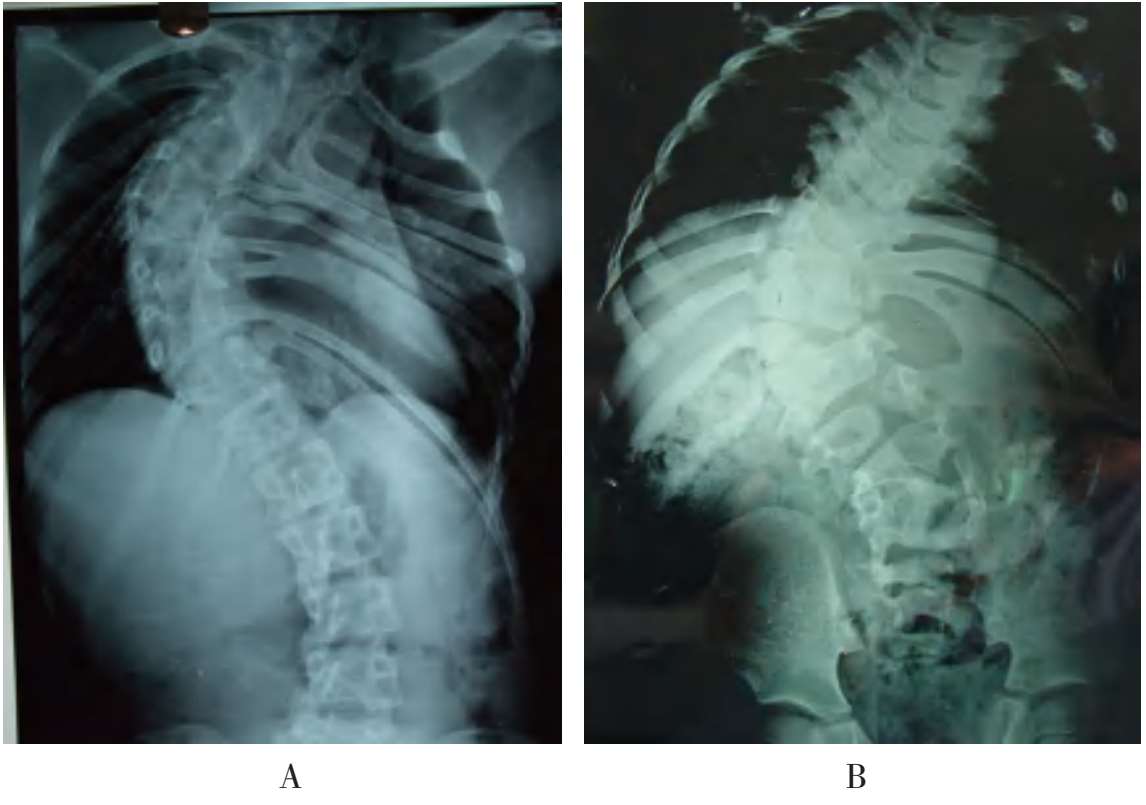

A.多发性并肋畸形;B.混合性并肋畸形

图3-25 脊柱侧弯合并肋骨畸形